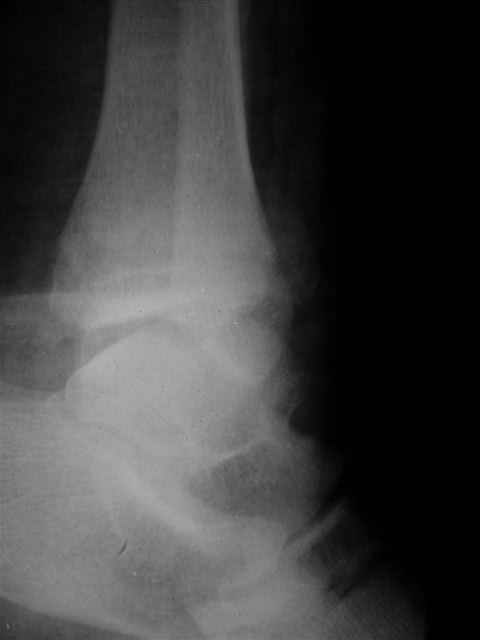

> Если Вас не затруднит, пришлите, пожалуйста, рентгенограммы. Я

> интересуюсь тактикой лечения повреждений голеностопного сустава.

Ничего сверхъестественного, но если есть интерес, то в понедельник пересниму Рг-граммы и отправлю.

Я предупреждал, что ничего сверхъестественного. Каюсь, что одна из спиц прошла несколько дальше, чем нужно было, но главное - перелом стабилизирован и больной работает суставом в полном объёме, несмотря на представленную раннее травму коленного сустава.